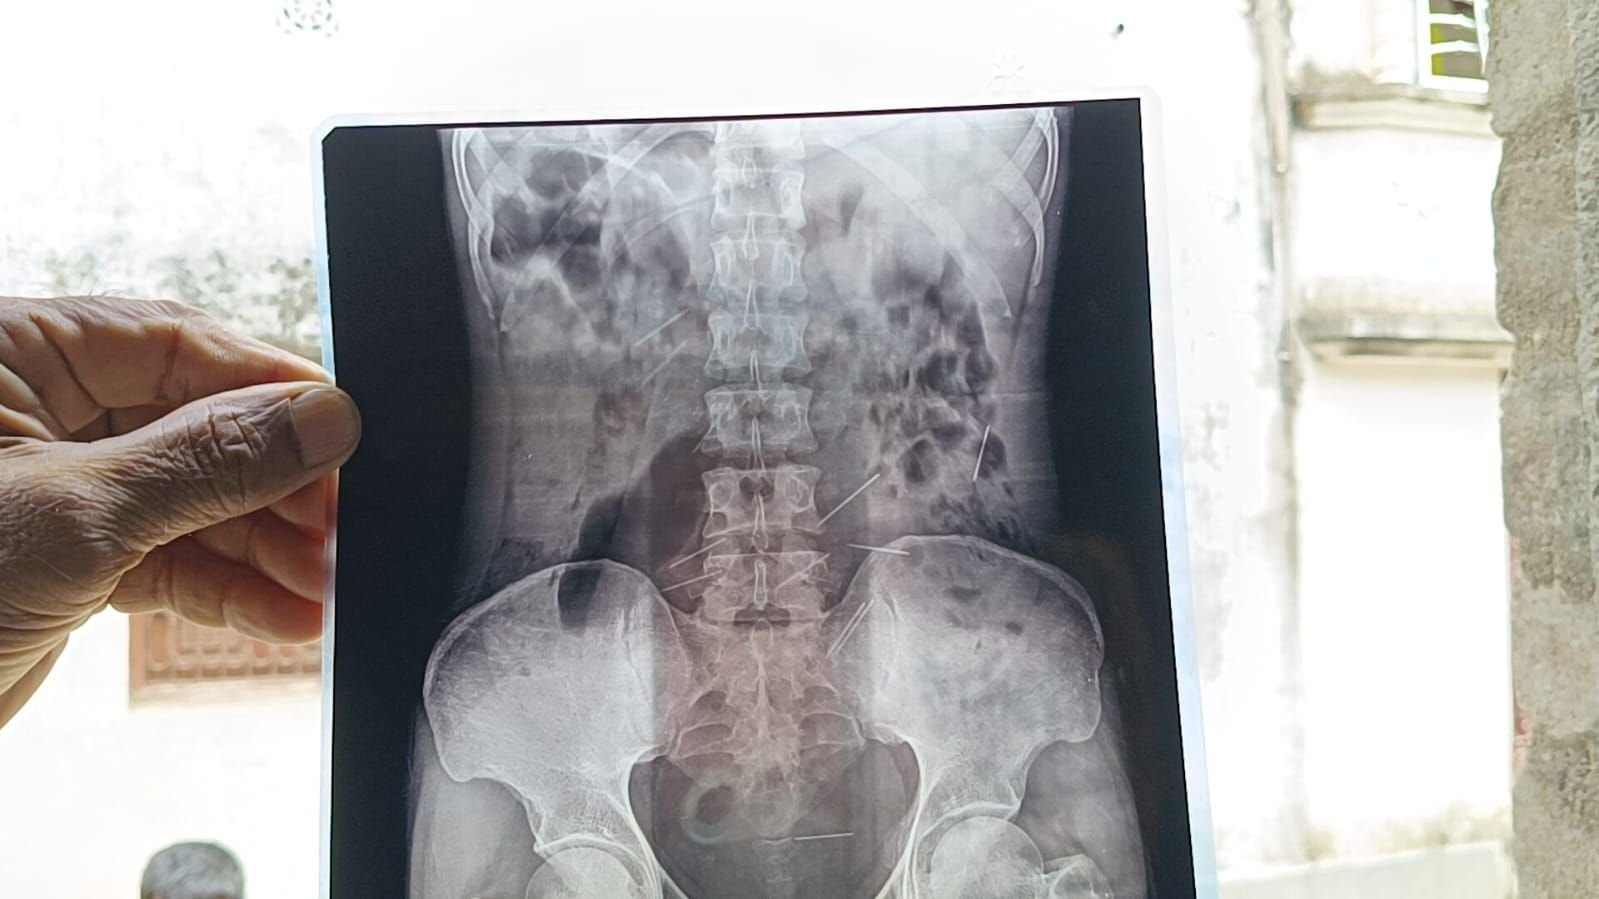

হায়দারের স্ত্রী নাসিমা খাতুন জানিয়েছেন, কয়েক মাস আগে মুর্শিদাবাদের সামশেরগঞ্জের একটি নার্সিংহোমে দু’দফা অপারেশন করে চিকিৎসকেরা হায়দারের শরীর থেকে মোট ৩৭টি সুচ বের করেছিলেন। চিকিৎসকেরা সেই সুচগুলো পরিবারকে দেখিয়েছিলেনও। নাসিমার অভিযোগ, “এখন পর্যন্ত বাড়ির সব জিনিসপত্র বিক্রি করে স্বামীর চিকিৎসা চালিয়ে গেছি, কিন্তু আর পেরে উঠছি না। কিভাবে শরীরে সুচ তৈরি হচ্ছে আমরা জানি না। আমাদের মনে হচ্ছে, কেউ কালা জাদুর মাধ্যমে ইচ্ছে করে শরীরে সুচ প্রবেশ করাচ্ছে।”